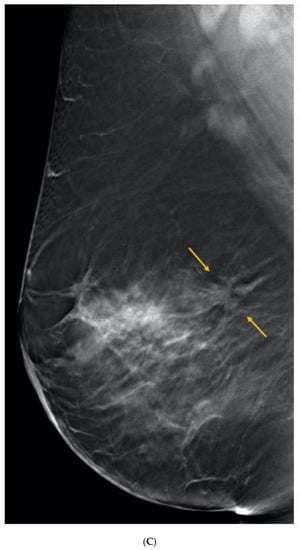

5. Ultrasound (US)

6. Digital Breast Tomosynthesis (DBT)

7. Magnetic Resonance Imaging (MRI)

8. Contrast-Enhanced Mammography (CEM)

9. Molecular Breast Imaging (MBI)